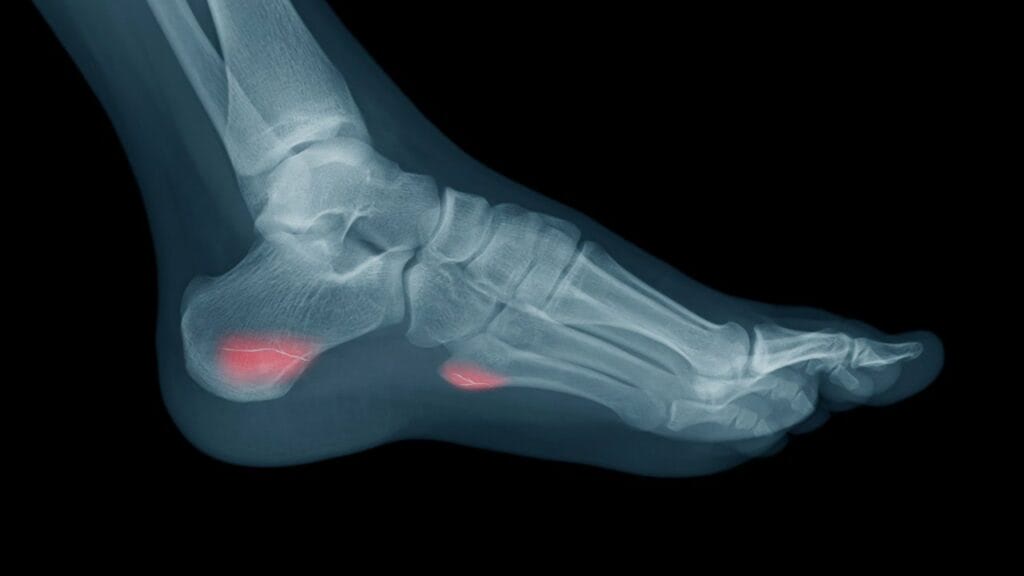

پزشک برای تشخیص شکستگی تنشی استخوان، سابقه پزشکی شما را بررسی می‌کند و معاینه فیزیکی انجام می‌دهد. همچنین ممکن است از اشعه ایکس یا سایر آزمایشات تصویربرداری برای تأیید تشخیص استفاده کند.

شکستگی استخوان